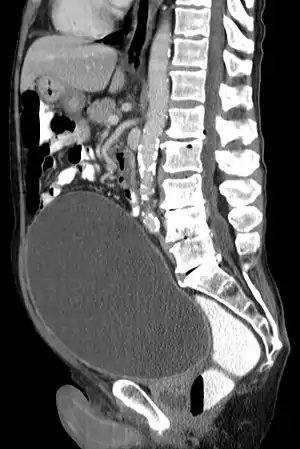

![]() | |

| Urinary retention with greatly enlarged bladder as seen by CT scan. | |

Analysis of urine flow may aid in establishing the type of micturition (urination) abnormality. Common findings, determined by ultrasound of the bladder, include a slow rate of flow, intermittent flow, and a large amount of urine retained in the bladder after urination. A normal test result should be 20-25 mL/s peak flow rate. A post-void residual urine greater than 50 ml is a significant amount of urine and increases the potential for recurring urinary tract infections. In adults older than 60 years, 50-100 ml of residual urine may remain after each voiding because of the decreased contractility of the detrusor muscle.[6] In chronic retention, ultrasound of the bladder may show massive increase in bladder capacity (normal capacity is 400-600 ml).